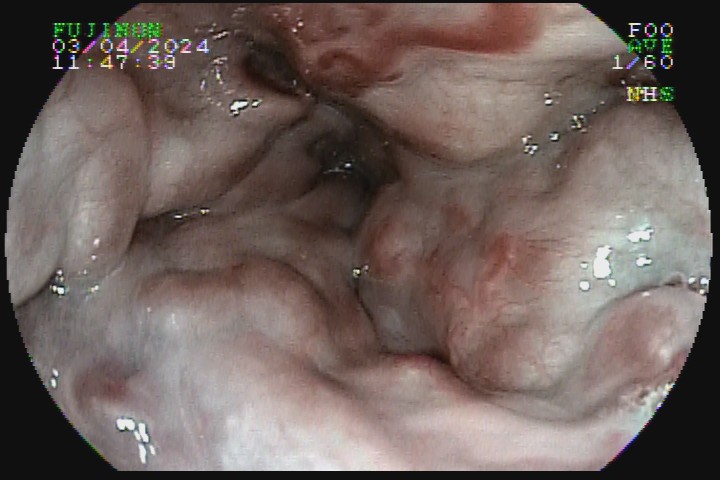

As varizes esofágicas devem ser classificadas em pequeno (<5mm), ou grosso calibre (>5mm), sendo esse o principal marcador prognóstico para o risco de sangramento e definição de conduta.

A presença de sinais da cor vermelha também é importante fator prognóstico. Eles surgem na superfície das varizes e são decorrentes da dilatação das vênulas superficiais, podendo ser em forma de vergão (red weal mark), de manchas cerejas (red spots) ou mancha hematocística.